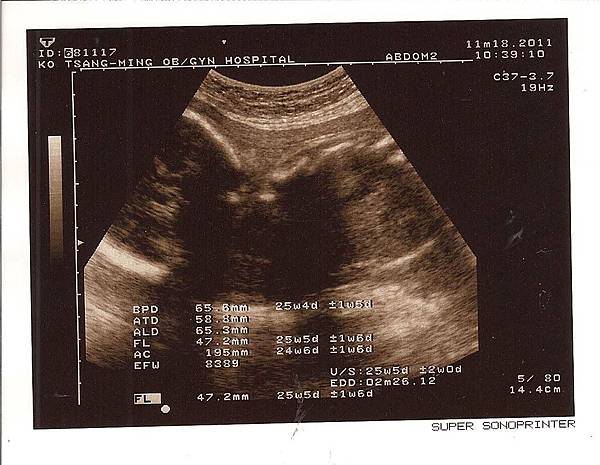

然後我們就開始照超音波 聽小Pi 的心跳

小Pi 這個月 還是有乖乖的長大

現在頭的寬度(BPD) 為 65.8 mm( 上個月: 58.4 mm)

腹圍(AC) 為 195 mm (上個月: 168 mm)

大腿骨長度(FL) 為 47.2 mm(上個月: 36.8 mm)

本周新增體重數值 為 838 g (我都想像這樣是多少豬肉在手上 :p)